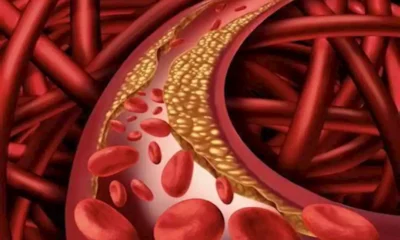

يشير خبراء التغذية إلى أن بعض المكملات العشبية يمكن أن تدعم بشكل معتدل خفض مستويات الكوليسترول في الدم، ما يجعلها خيارا مساعدا أو بديلا لبعض الأشخاص...